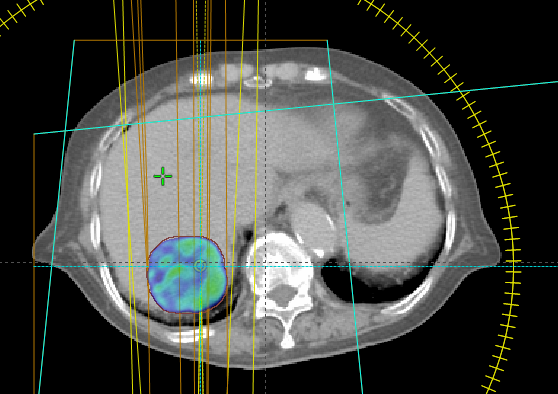

立體定位放射治療技術的特點是極高精準度,治療療程為高劑量、少次數。因為治療次數少,治療天數大幅縮短;因為極高精準度及單次劑量高,治療副作用輕微且療效佳(臨床適用於早期肺癌、肝腫瘤或低數量轉移、腦部轉移或腫瘤、或是轉移腫瘤,詳細相關適應症需諮詢放射腫瘤科醫師),下方案例為早期肺癌及肝腫瘤立體定位放射治療。

案例二 肝腫瘤立體定位放射治療